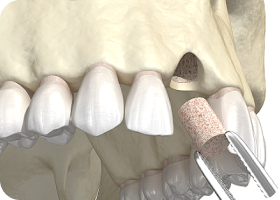

Q. 뼈이식 임플란트는 어떻게 치료하나요?

잇몸뼈는 임플란트를 지지하는 중요한 기반입니다. 하지만 시간이 지나거나 잇몸병으로 뼈가 약해진 경우엔

임플란트를 바로 심기 어렵습니다. 이럴 땐 부족한 뼈를 이식해 튼튼한 기반을 만든 뒤, 임플란트를 심는 정밀 치료입니다.

바른선택 뼈이식 STAGE 01

세심한 사전 진단 및 식립 계획

뼈 상태와 구강 구조를 분석을 기반으로

가장 안전한 위치에 임플란트를

식립할 수 있도록 시술 계획을 수립합니다.

바른선택 뼈이식 STAGE 02

뼈 이식 수술 진행

잇몸뼈가 부족한 부위에 이식재를 넣어

뼈를 보강하고, 기존 뼈와 융합될 수 있도록

안정화를 유도합니다.